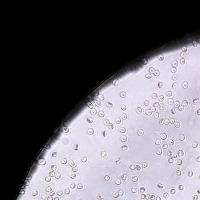

RBC Platelet v1 Computer Vision Project

Medical Diagnostic Tools: "RBC Platelet v1" can be integrated into diagnostic software systems to help physicians automatically detect and classify blood cells, aiding in faster disease diagnosis such as anemia, leukemia, or thrombocytopenia.

Biological Research: Researchers studying blood cells and diseases could use this model to automate cell identification and classification in their lab results, making for a more efficient research process.

Educational Purposes: The model can be used in educational applications or e-learning platforms to help students in fields such as medical sciences and biology get to know the different types of cells and their characteristics.